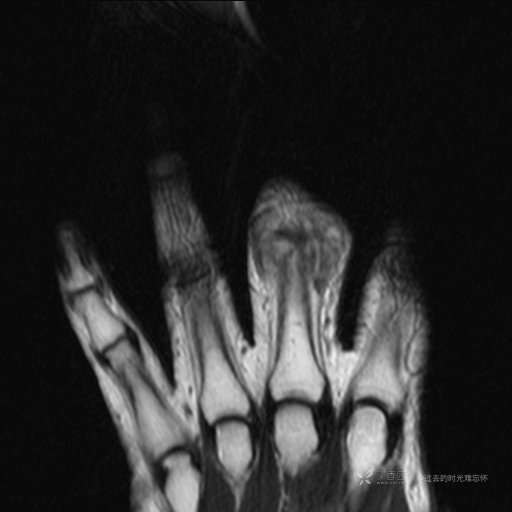

患者性别:女

患者年龄:59岁

主诉: 手指肿胀2年,其间明显肿胀,抗炎后肿胀减轻,近几日肿胀疼痛加重。

T2及T2压脂